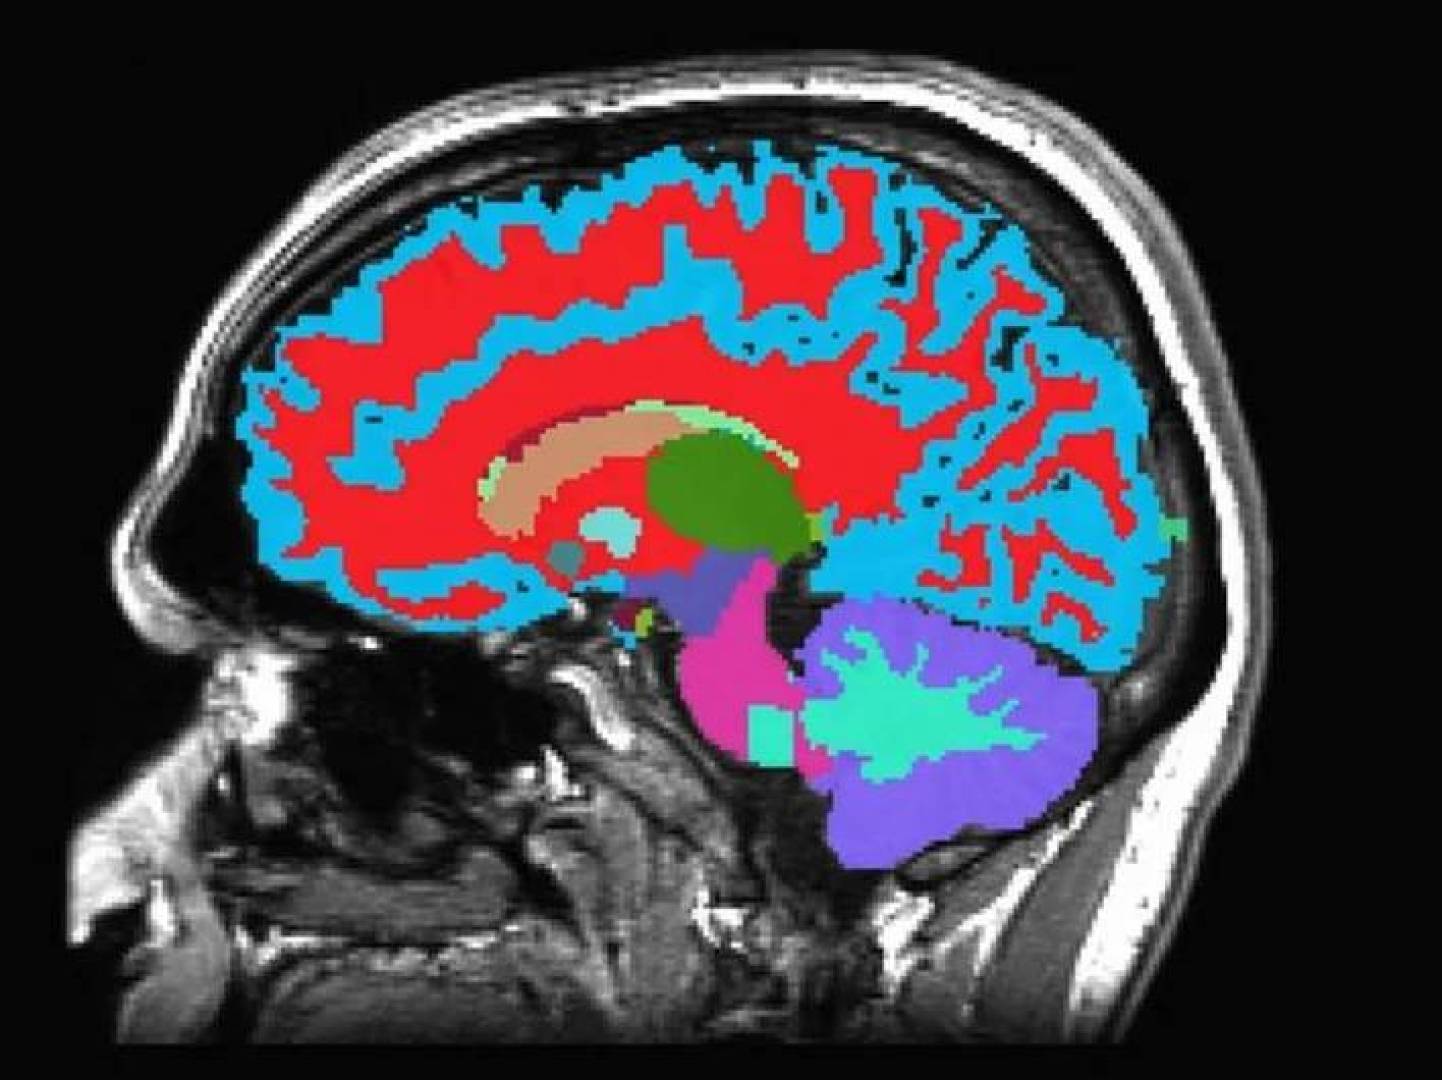

تأثير فيروس كوفيد-19 على الدماغ ( مصدر الصورة: Eurekalert.org )

اعتمد الباحثون على التصوير بالرنين المغناطيسي عالي الدقة (MRI) لمقارنة أدمغة أشخاص أُصيبوا سابقا بكوفيد-19 مع آخرين لم يتعرضوا للفيروس ، واستخدم الفريق ما يُعرف بـالتصوير متعدد الأنماط، وهي تقنية متقدمة تسمح بتحليل:

بنية أنسجة الدماغ

التغيرات الكيميائية العصبية

نشاط المادة الرمادية والبيضاء

وتركز التحليل على المناطق المسؤولة عن:

الذاكرة

التركيز والانتباه

الوظائف الإدراكية العليا